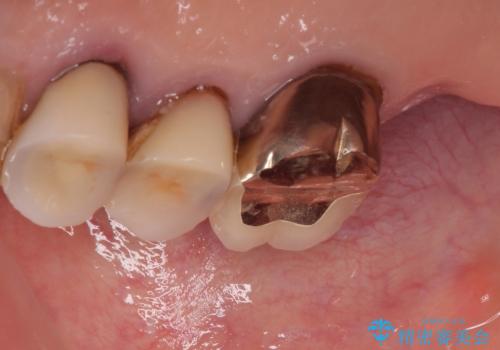

- 食事が取れないほどの激痛で、インプラント治療を希望して来院された患者様です。

近医にてクラウンを除去してもらった状態での来院でした。

遠心が歯根破折しており、歯槽骨が著しく吸収している状態であったため、抜歯即時でのインプラント埋入は断念し、2ヶ月ほど待機してから埋入することとしました。